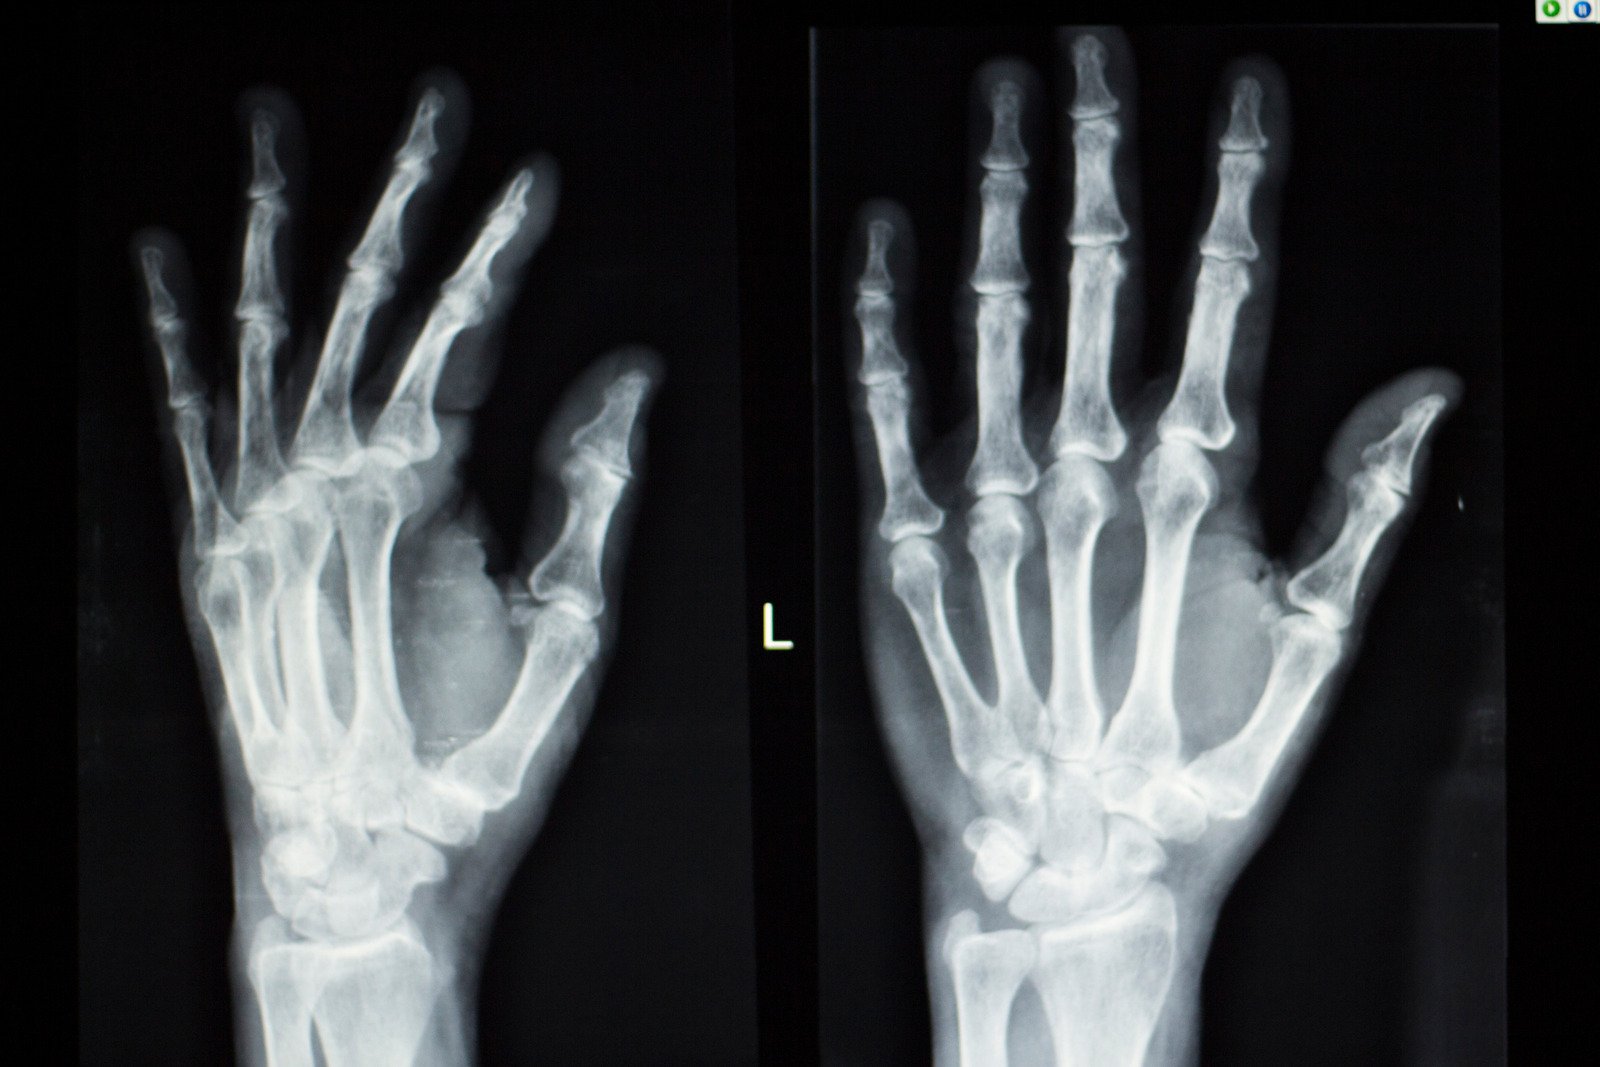

골연령(Bone Age)은 뼈의 성숙도를 기준으로 나이를 평가하는 방법으로, 주로 손목의 뼈를 엑스레이로 촬영한 후 그 성숙도를 표준 자료와 비교하여 판단합니다. 골연령은 실제 연령과 다를 수 있으며, 이는 아이의 성장 상태에 대한 중요한 정보를 제공합니다.

가장 흔히 사용하는 방법은 Greulich-Pyle 방법으로, 손과 손목의 뼈를 촬영하여 골연령을 평가합니다. 검사 방법은 다음과 같습니다.

엑스레이 촬영: 환자의 왼손과 손목을 방사선으로 촬영합니다. 이 부위는 성장판이 뚜렷하게 나타나고, 뼈 성숙도를 비교하기에 적합하기 때문에 주로 사용됩니다.

골연령 평가: 엑스레이 결과를 Greulich-Pyle 표준 도표 또는 Tanner-Whitehouse 방법에 따라 분석합니다. 이는 연령별로 뼈의 성숙도를 기준화한 자료와 비교하는 방식입니다. 뼈의 모양, 크기, 성장판의 닫힌 정도 등을 평가하여 아이의 골연령을 결정합니다.